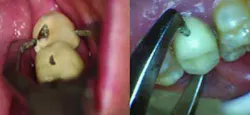

Fig. 2 — Dimples act as receptacles for beaks of Baade pliers.Once the dimples are made and the Baade pliers are in position (Fig. 3), the operator attempts to break the cement seal and remove the crown with a twisting motion of the hand and wrist. This technique works especially well on teeth with short clinical crowns and/or teeth that have been prepared with excessive taper. If the crown resists displacement using this technique, it is unwise to attempt to force the crown off with the Baade pliers, as the tooth may fracture. The dimple technique is also contraindicated on teeth with advanced loss of periodontal attachment, unfavorable crown-to-root ratio, or excessive mobility. In these cases, the crown should be sliced from the buccal gingival margin to the occlusal or incisal aspect and then pried off with a narrow-ended hand instrument.